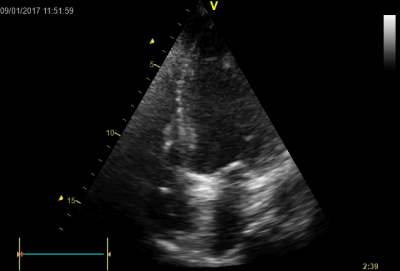

Video 1 - Akutní koronarografie prokázala normální nález na věnčitých tepnách s výjimkou suspekce na lehký spasmus na pravé koronární tepně.Echokardiograficky byla zjištěna těžká dysfunkce dilatované levé komory s nezvětšenou pravou komorou (video 2).

Video 2 - Echokardiograficky byla zjištěna těžká dysfunkce dilatační levé komory s nezvětšenou pravou komorou.Pro nejasnou příčinu zástavy jsme provedli i vyšetření výpočetní tomografií (CT), které vyloučilo plicní embolizaci (série 1 - soubory na konci článku). V den přijetí při přetrvávající oběhové nestabilitě byla nemocná opakovaně defibrilována pro fibrilaci komor se stabilizací rytmu po podání amiodaronu a mesocainu. Dle hemodynamických měření se jednalo o těžký kombinovaný šok. Vstupní laboratorní vyšetření bylo bez větších pozoruhodností. Posléze jsme doplnili anamnézu od příbuzných a zjistili, že pacientka užila do dvou hodin před srdeční zástavou první tabletu amoxicilinu na lehký respirační infekt. Při nevýtěžnosti vstupních vyšetření a nových anamnestických informacích jsme doplnili 14 hodin po kolapsu vyšetření koncentrace tryptázy v séru, která byla extrémně zvýšena (tabulka 2), což nás vedlo k podezření na anafylaxi.

Na kůži byl nápadný, v čase proměnlivý hnědočervený makulopapulózní exantém s převahou na předních a laterálních partiích stehen a na podbřišku, pro který byla nemocná vyšetřována již v minulosti bez jasného výsledku. Koncentrace tryptázy v séru v kontrolních odběrech byla překvapivě zvýšena nadále i v odstupu několika dnů (tabulka 2), ačkoliv při anafylaxi jsou hodnoty zvýšeny pouze v období do čtyř až šesti hodin. Vzhledem k suspektnímu dermatologickému nálezu, který imponoval jako urticaria pigmentosa, a ke zvýšení bazální tryptázy padlo podezření na systémovou mastocytózu. Zahájili jsme proto příslušnou léčbu antihistaminiky (levocetirizin). Stav se postupně zlepšoval a šestý den hospitalizace jsme pacientku extubovali, nedošlo k poškození mozku (cerebral performance category scale 1 [CPC-1]) a při současné terapii milrinonem se zlepšila i ejekční frakce levé komory z 25 % na 55 % (video 2–4); dobrá funkce levé komory přetrvávala i po vysazení inotropik.

Video 2 - Echokardiograficky byla zjištěna těžká dysfunkce dilatační levé komory s nezvětšenou pravou komorou. Video 3 Video 4Molekulárně-genetické a imunohistologické vyšetření kostní dřeně potvrdilo systémovou mastocytózu, typ smouldering, c-KIT pozitivní.